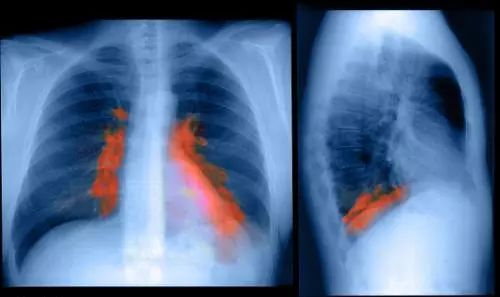

肺部感染

长期卧床,患者咳嗽、咳痰能力下降,往往易并发生坠积性肺炎。除了可引起败血症、毒血症、呼吸窘迫外,还可能增加心脏负担,引起肺源性心脏病。